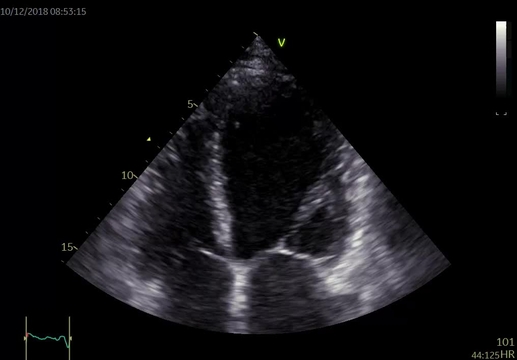

Při fyzikálním vyšetření měla nemocná TK 115/70 mm Hg, pravidelný puls 100/min, poslechově na plicích inspirační chrůpky při bázích a systolický šelest v prekordiu s maximem na hrotu, bez jasné propagace, intenzity 3/6. Dolní končetiny jsou se symetrickými perimaleolárními otoky, klidné varixy. Na EKG byla přítomna sinusová tachykardie 105/min, EKG kritéria hypertrofie levé komory s mírnými repolarizačními změnami, bez signifikantní ST denivelizace a abnormalita levé síně (obrázek 1). Echokardiografie prokázala dilataci a excentrickou hypertrofii levé komory (LVEDD 63 mm, LVMI 102 g/ m2, relativní tloušťka stěn 0,35), difúzní hypokinezi stěn výraznější v oblasti septa a těžkou systolickou dysfunkci levé komory s EF 24 %. Diastolická funkce měla charakter pseudonormalizace se zvýšenými plnicími tlaky levé komory (E/e'průměr 13). Dále byla zjištěna středně významná sekundární mitrální regurgitace 2–3+ při dilataci anulu a restrikci cípů v důsledku remodelace levé komory a sekundární trikuspidální regurgitace 2–3+ při dilataci anulu (video 1 a 2). Levá síň byla dilatována s indexovaným objemem 48 ml/m2 a zvýšena byla tenze v plicnici s odhadem PASP 49 mm Hg. Laboratorně prokázána elevace NT-proBNP 4 170 ng/l, mírná hypokalémie 3,6 mmol/l, kreatinin 112 μmol/l s mírně sníženou glomerulární filtrací 70 ml/min/1,73 m2 dle MDRD.

Video 2. Echokardiografické vyšetření – středně významná sekundární mitrální regurgitace 2–3+